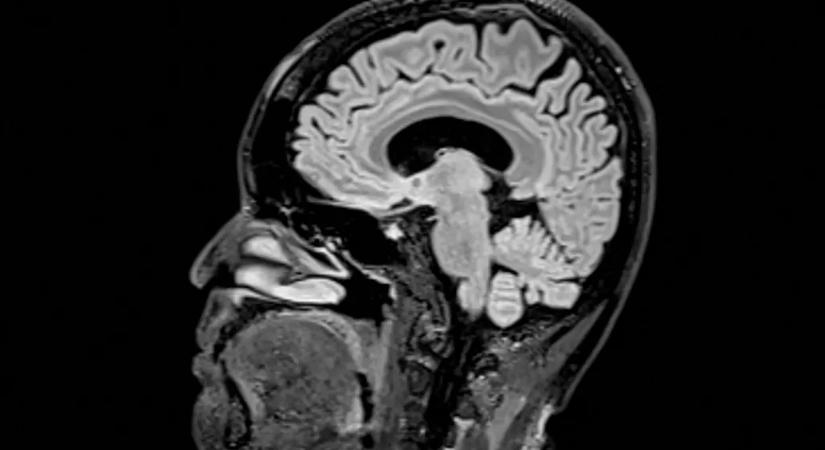

Egy friss kutatás szerint az agyi fejlődés öt különböző érába sorolható, és mindegyikben más változások a legjellemzőbbek.